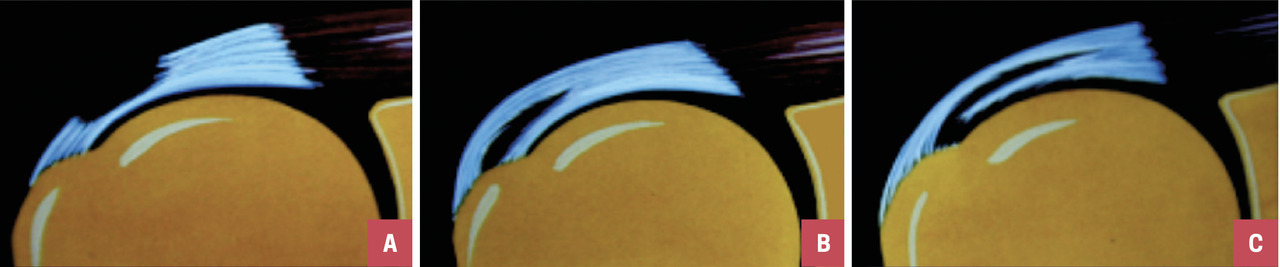

On distingue différentes lésions tendineuses   : non rompues, on parle alors de tendinopathies ; ou rompues, la rupture pouvant être partielle ou transfixiante (fig. 2 et 3).

• une rupture partielle (de tous types, fig. 2) ;